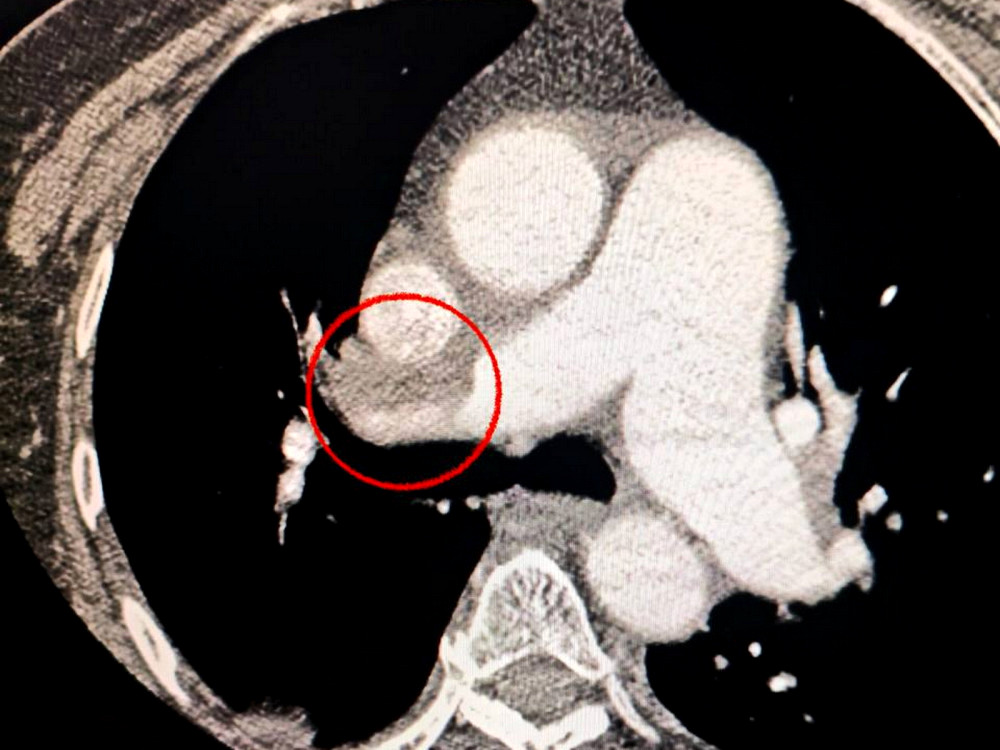

Пацієнтка потрапила в лікарню з серйозним гострим мозковим інсультом. Під час комп'ютерної томографії медики виявили закриття середньої мозкової артерії.

Лікарі також помітили, що жінка мала труднощі з диханням, тому провели додаткове обстеження легень. Виявилося, що у неї також тромбоемболія легеневої артерії.